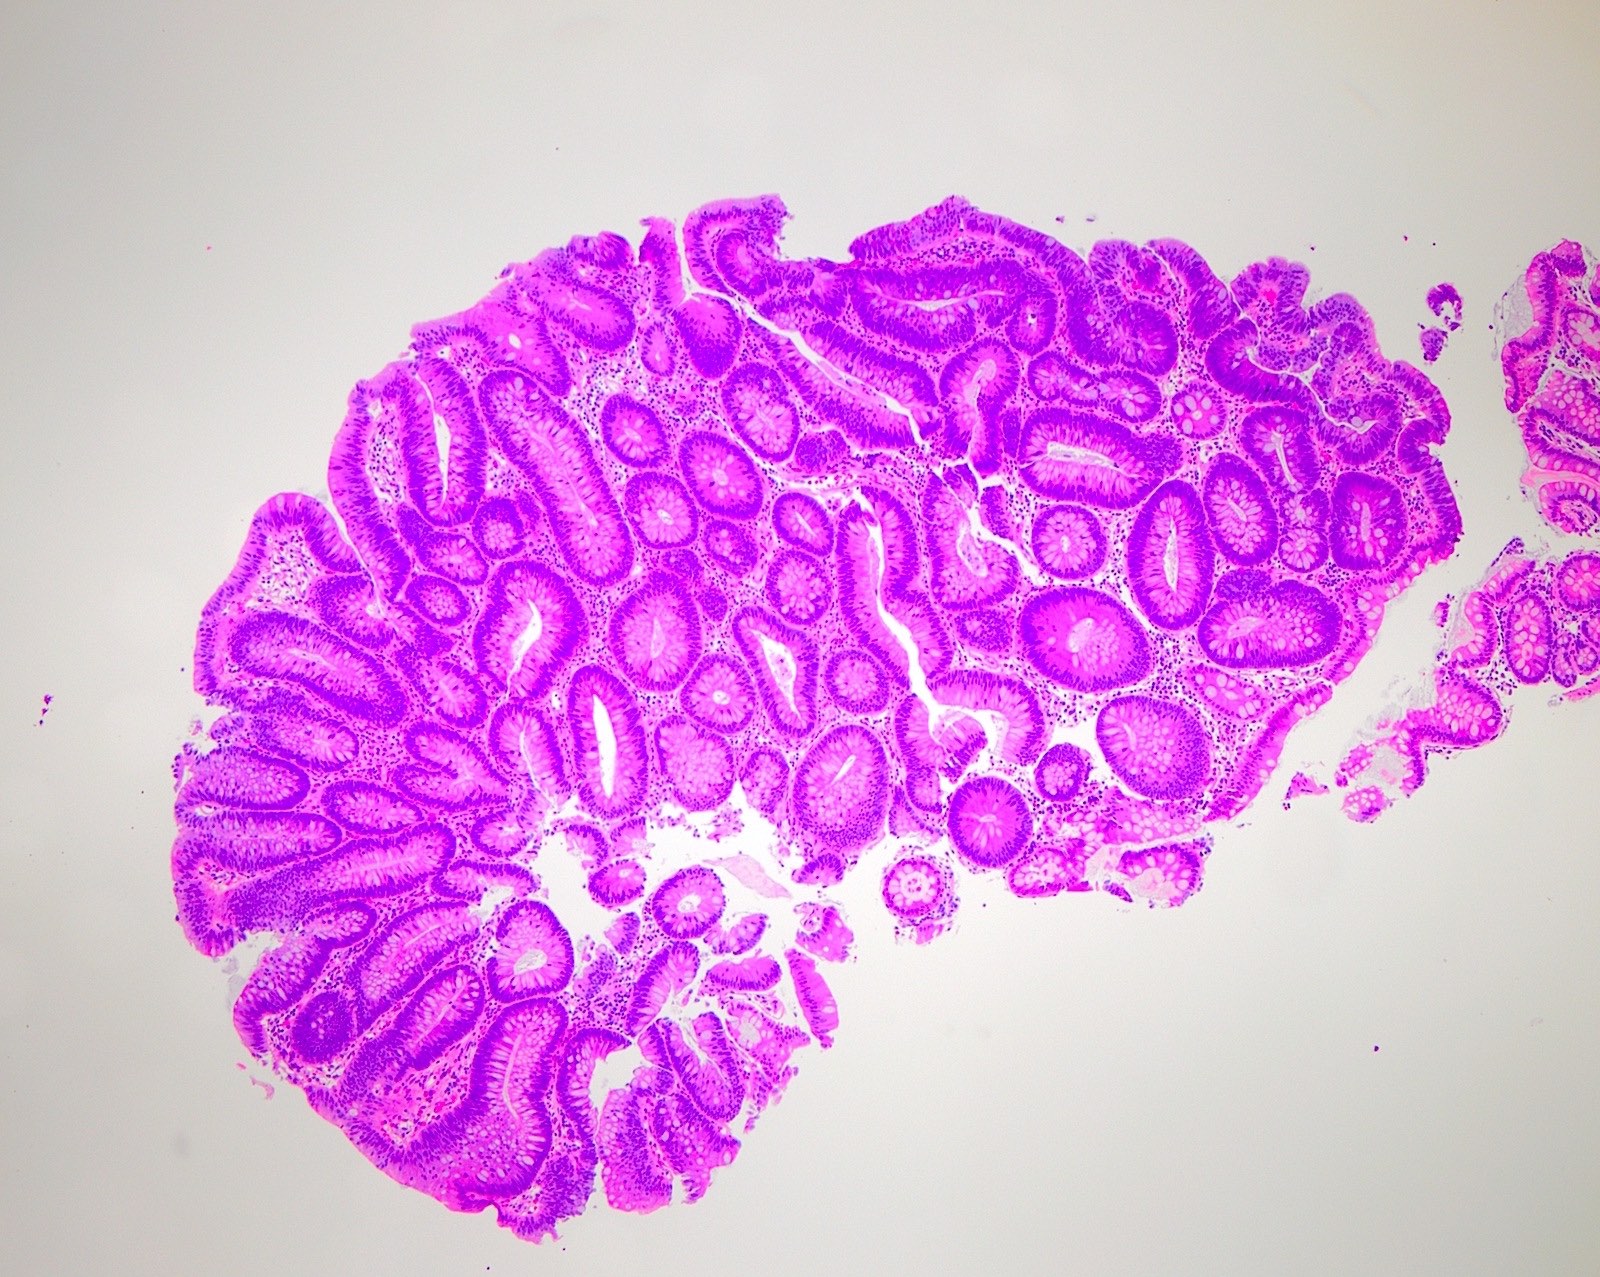

Microscopic (histologic) description

- Polypoid colonic mucosa covered with dysplastic epithelium comprised of hyperchromatic, elongated nuclei arranged in a pseudostratified manner

- Dysplasia is typically low grade but may also be high grade, with architectural (cribriforming, luminal necrosis) and cytologic changes (vesicular chromatin, nucleoli, loss of basal polarity)

- Abrupt transition from normal to dysplastic mucosa is commonly present

- Variable amounts of mucin loss

- Metaplasia may be present: osseous, squamous or Paneth cells (J Clin Pathol 2005;58:220, J Surg Oncol 1984;26:130)

- Pseudoinvasion can mimic progression to adenocarcinoma but displaced glands are benign and surrounded by lamina propria and often hemosiderin (Mod Pathol 2015;28:S88)

Microscopic (histologic) images

Contributed by Andrew L.J. Dunn, M.D. and Christopher Hartley, M.D.

Contributed by @Andrew_Fltv and @liverwei on Twitter